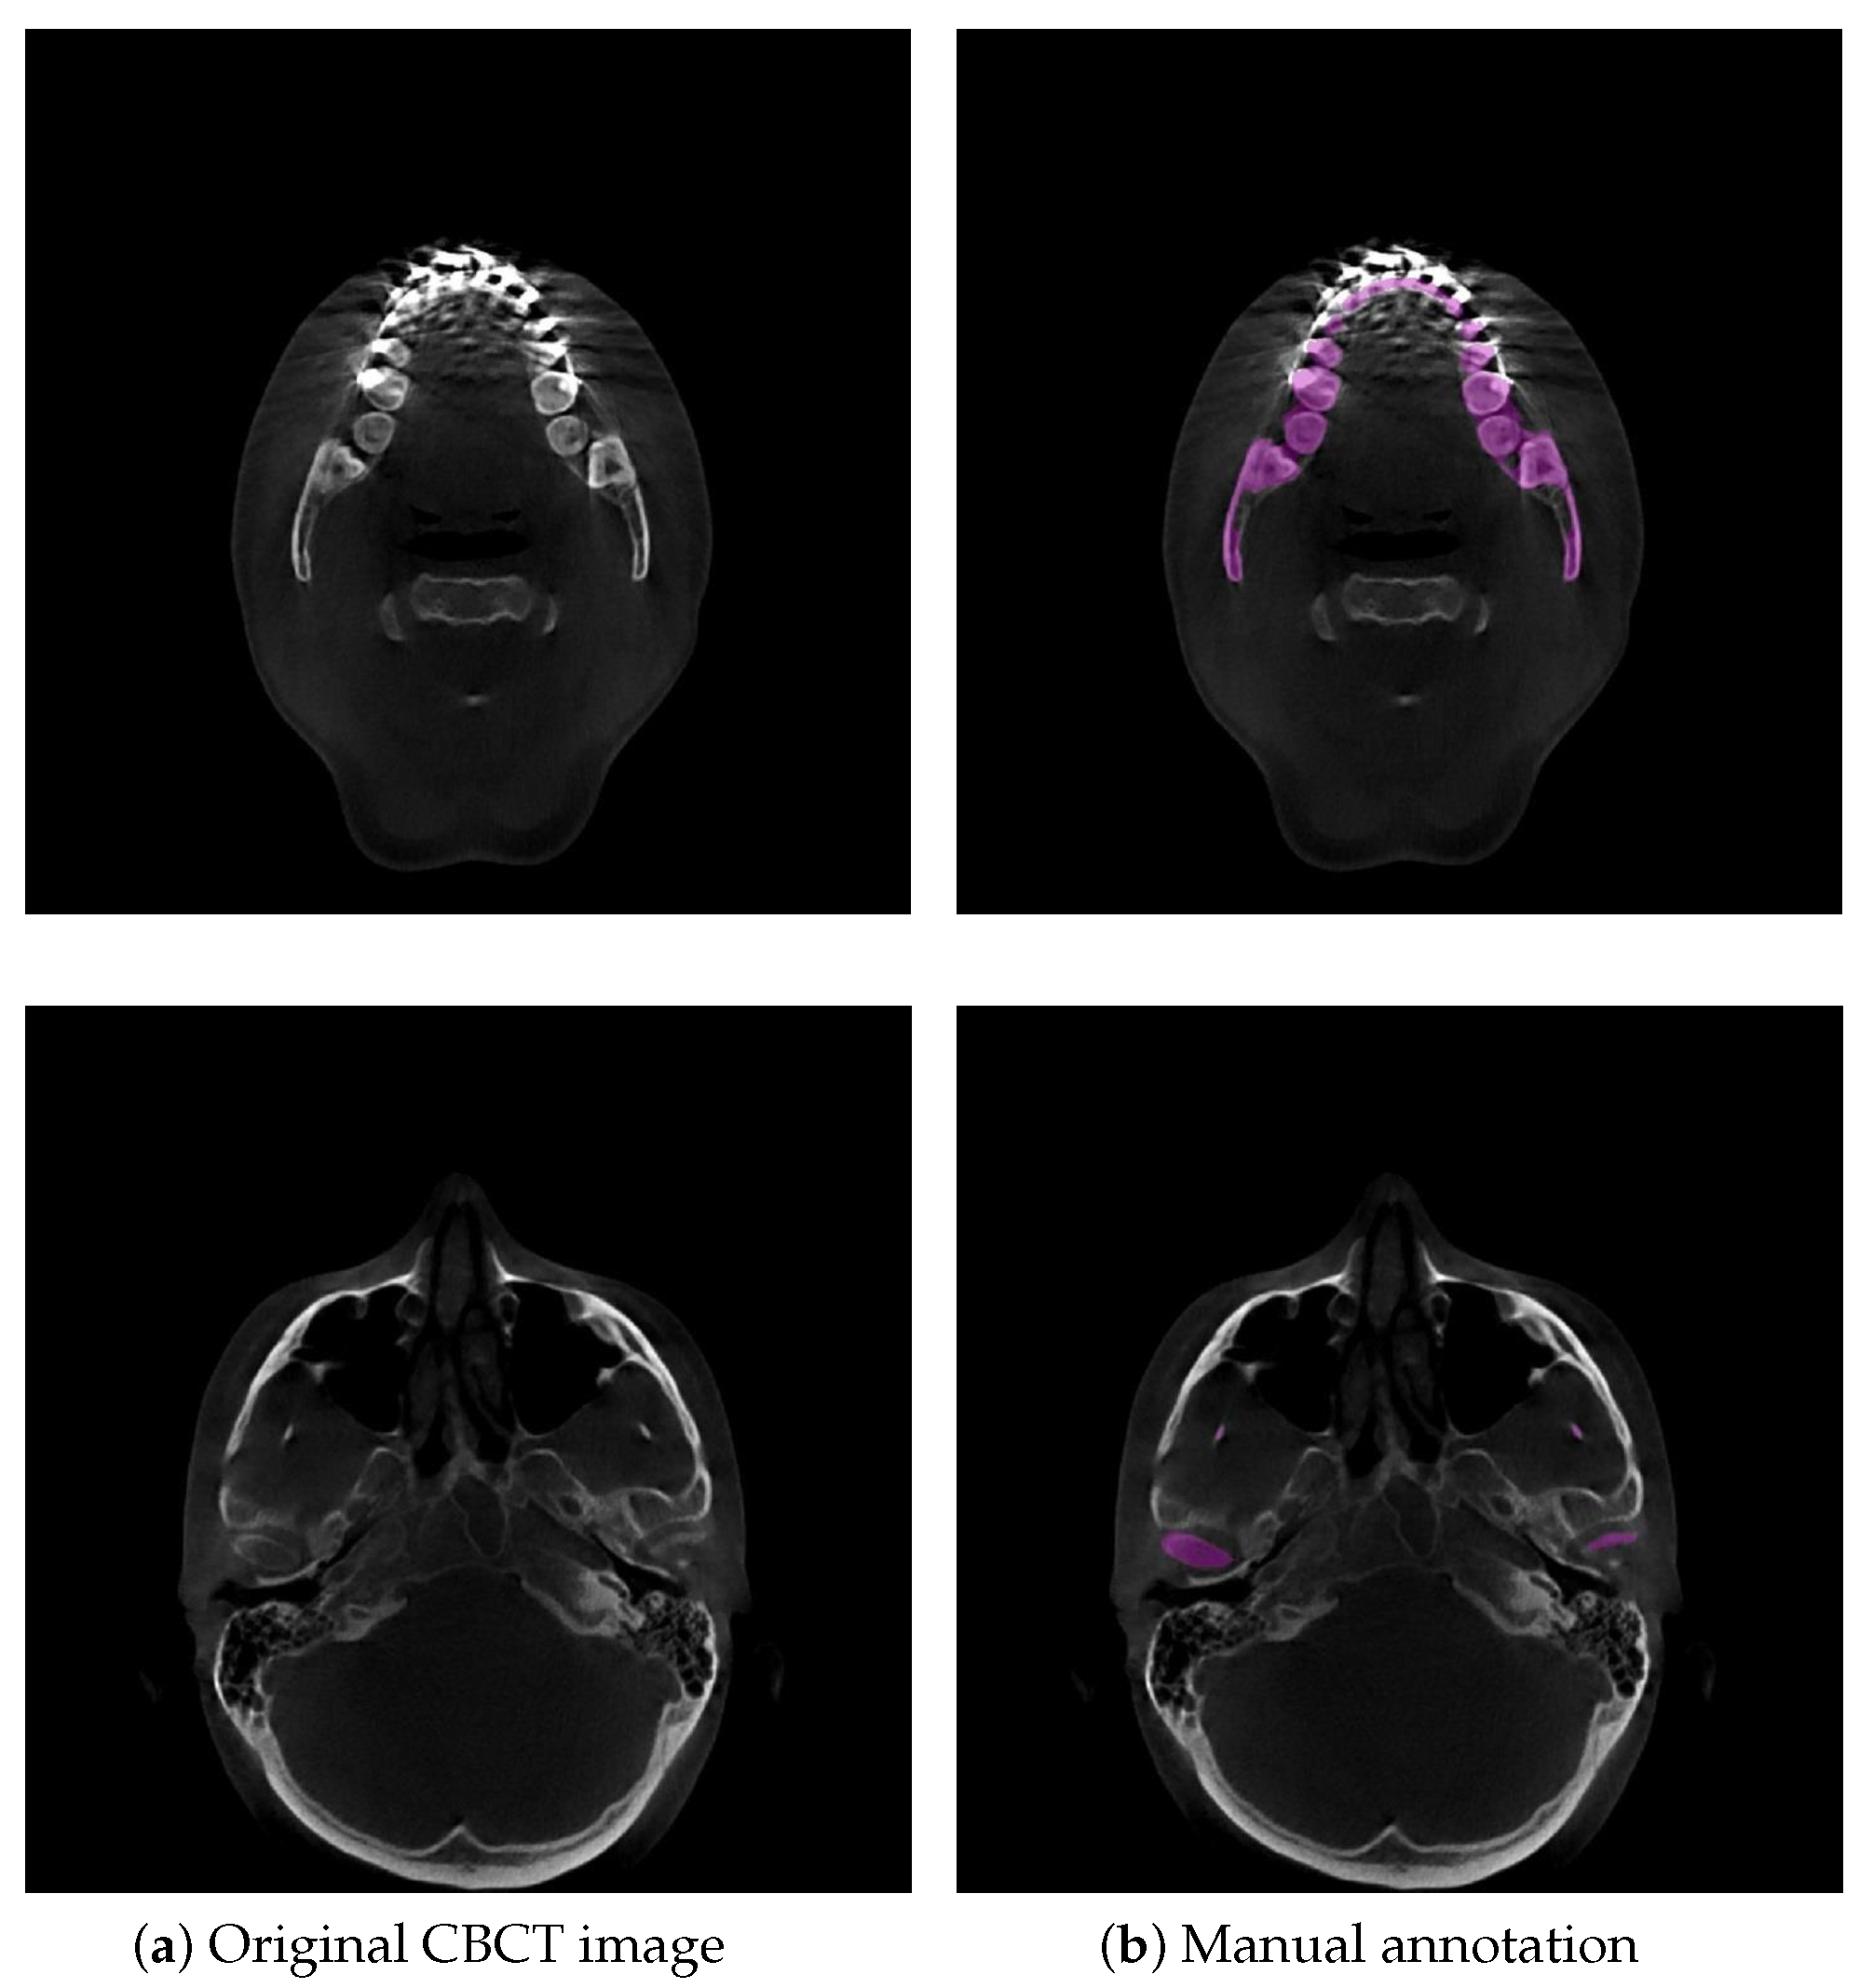

2.5. Dataset